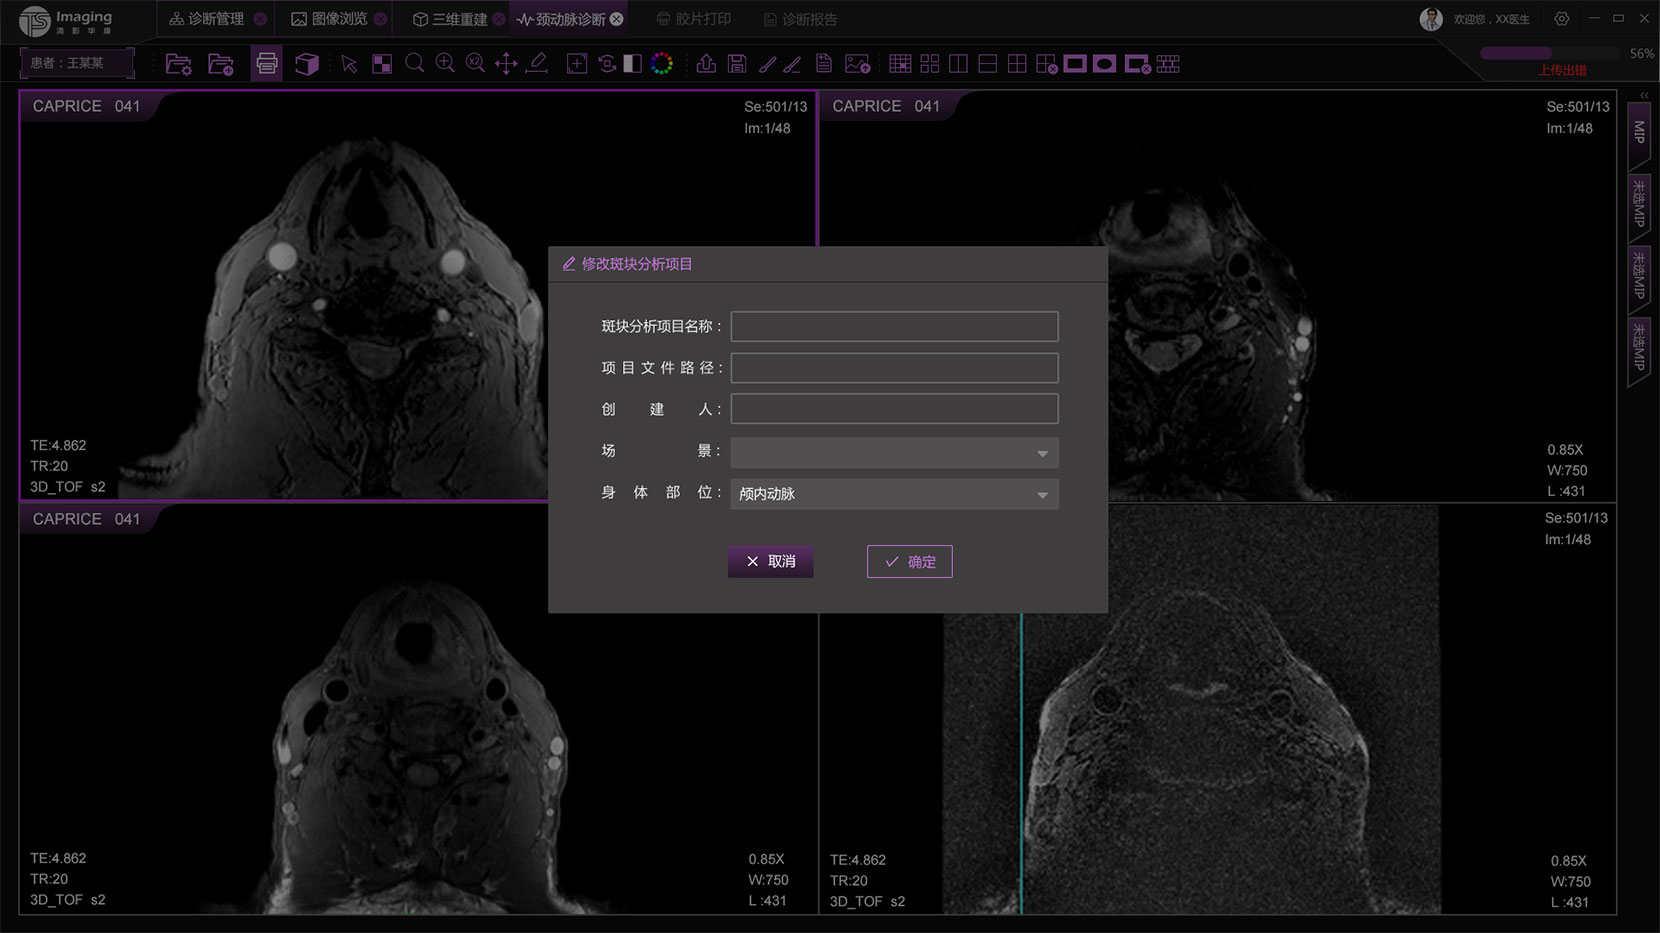

頸動脈診斷頁面

頸動脈診斷頁面整體布局和三維重建比較相似,最大的區別是右側的操作區域,血管分析都為按鍵操作,通過間隔的大小分成三部分。單層切片除了按鍵還有下拉菜單的操作。

頸動脈診斷原型